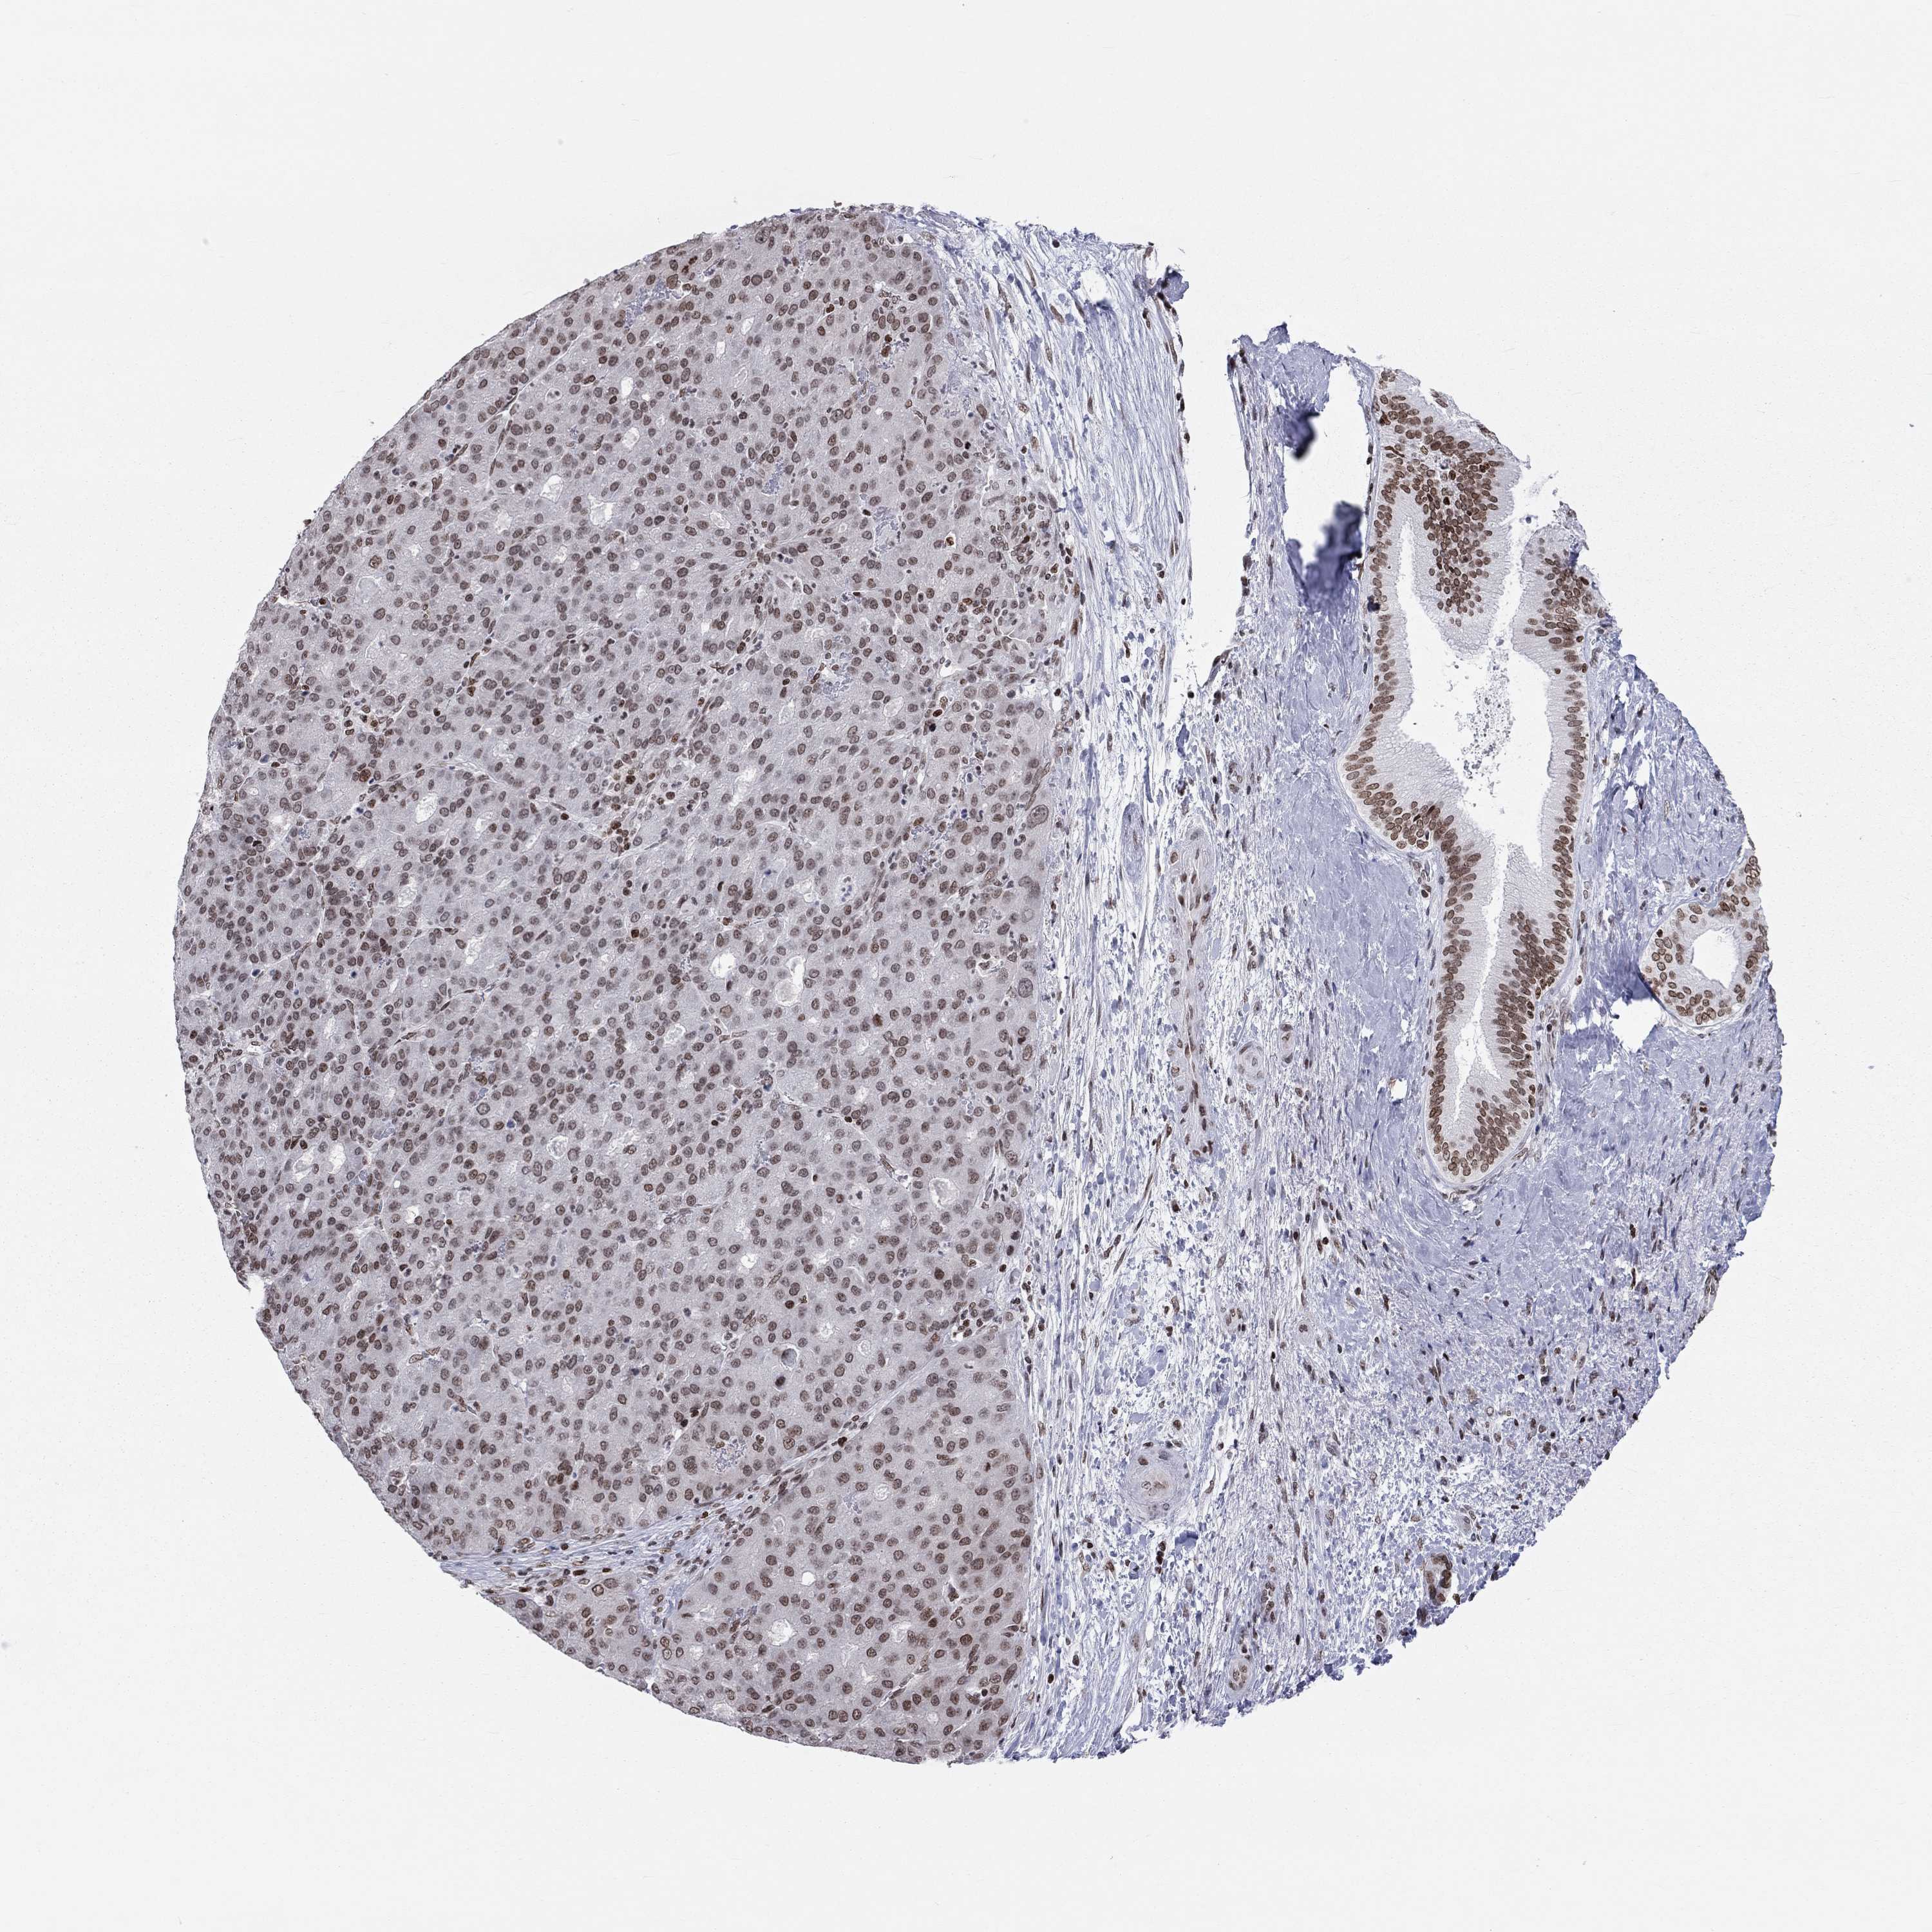

LIVER CANCER - Protein expressioni

A mouse-over function shows sample information and annotation data. Click on an image to view it in a full screen mode. Samples can be filtered based on level of antibody staining by selecting one or several of the following categories: high, medium, low and not detected. The assay and annotation is described here.

Note that samples used for immunohistochemistry by the Human Protein Atlas do not correspond to samples in the TCGA dataset.

Antibody stainingi

Antibody staining in the annotated cell types in the current human tissue is reported as not detected, low, medium, or high, based on conventional immunohistochemistry profiling in selected tissues. This score is based on the combination of the staining intensity and fraction of stained cells.

Each image is clickable and will lead to virtual microscopy that enables deeper exploration of all samples and also displays staining intensity scores, fraction scores and subcellular localization as well as patient and tissue information for each sample.

Antibody HPA041189

Antibody HPA051647

Antibody CAB012264

Staining

High

Medium

Low

Not detected

Intensity

Strong

Moderate

Weak

Negative

Quantity

>75%

75%-25%

<25%

None

Location

Nuclear

Cytoplasmic/membranous

Cytoplasmic/membranous,nuclear

Cholangiocarcinoma

Carcinoma, Hepatocellular, NOS